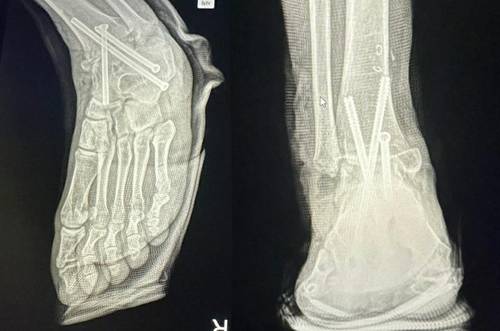

보도에 따르면, A 씨는 2시간여의 수술이 끝나고 마취에서 깨어나 보니 멀쩡하던 오른 발목뼈가 잘리고 철심 3개가 박혀있었다고 한다. 그는 즉시 경찰에 신고해 의료과실의 증거를 확보한 후 다시 왼발 수술을 받았다.

![병원 실수로 멀쩡한 발목뼈를 절단해 철심 3개를 박은 모습복숭아뼈를 절단해 아래의 뼈들과 고정했다. 이 때문에 발목을 구부리거나 펴기가 어려워 정상적으로 걷지 못하게 됐다. [연합. A씨 제공]](https://img4.daumcdn.net/thumb/R658x0.q70/?fname=https://t1.daumcdn.net/news/202312/16/ned/20231216100612340inkv.jpg)

B 병원은 그동안 A 씨의 병원비를 받지 않았고 그의 재활치료를 돕기 위해 병원 근처에 월세방도 얻어주었다. 그러나 A 씨의 오른발은 복숭아뼈를 잘라 여러 뼈를 철심으로 연결해 발목이 움직이지 못하도록 고정해 놓았는데, 지금은 뼈들이 다 굳어진 상태이며 과거의 온전한 모습으로 돌아가기 어렵다고 한다.